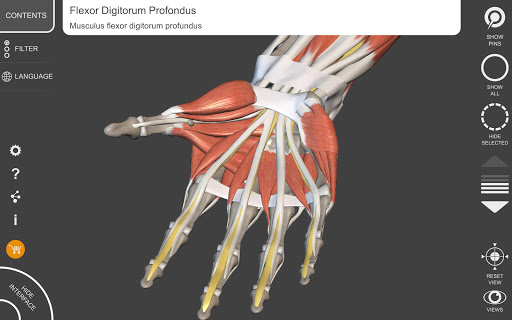

"Anatomy 3D Atlas" дозволяє легко та інтерактивно вивчати анатомію людини.

Завдяки простому та інтуїтивно зрозумілому інтерфейсу можна спостерігати кожну анатомічну структуру під будь-яким кутом.

Анатомічні 3D-моделі особливо деталізовані та мають текстури з роздільною здатністю до 4k.

АНАТОМІЧНІ 3D МОДЕЛІ

• Кістково-м’язова система

• Обертайте та збільшуйте кожну модель Тривимірний простір

• Візуалізація м’язів через рівні шарів від поверхневих донизу до найглибших

• Вибравши модель або шпильку, з’явиться відповідний анатомічний термін

• Опис м’язів: походження, приєднання, іннервація та дія